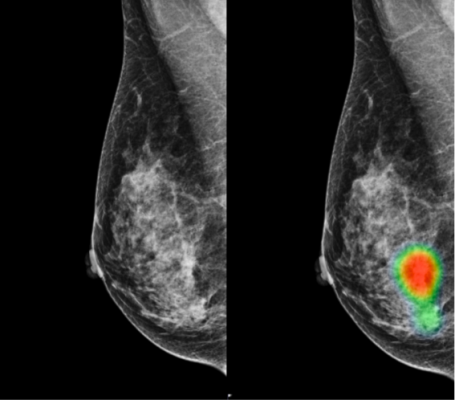

- மாமோகிராபி (Mamography)

- 50 முதல் 70 வயது வரை உள்ள அனைத்து பெண்மணிகளும் 3 வருடத்திற்க்கு ஒருமுறை இந்த பரிசோதனை செய்து கொள்வது நன்று.